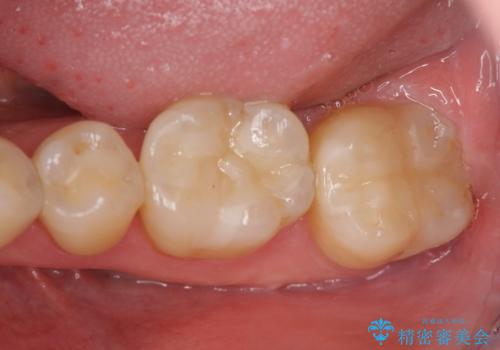

- 笑った時に見える下顎の銀歯を白くしたいと希望され来院されました。

銀歯を丁寧に外したのち、セラミックインレーによる修復を計画します。

笑った時に見える銀歯を白くすることで口の中が明るい印象になります。